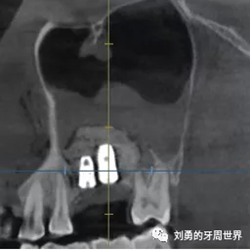

在手術(shù)之前行ct檢查如下圖:

可見B5種植體已經(jīng)脫落進(jìn)入上頜竇,而上頜竇黏膜已經(jīng)出現(xiàn)明顯的炎癥,上頜竇黏膜明顯增厚,(在二期切開手術(shù)之前上頜竇黏膜厚度正常)。而在ct上可以看到左側(cè)上頜竇中鼻道開口不通暢。